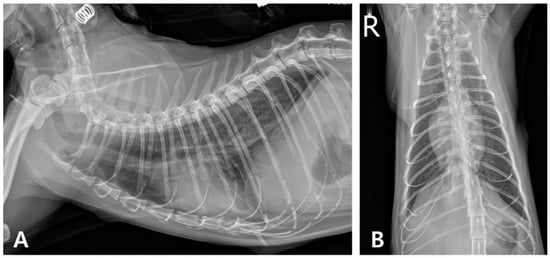

2. Case Description